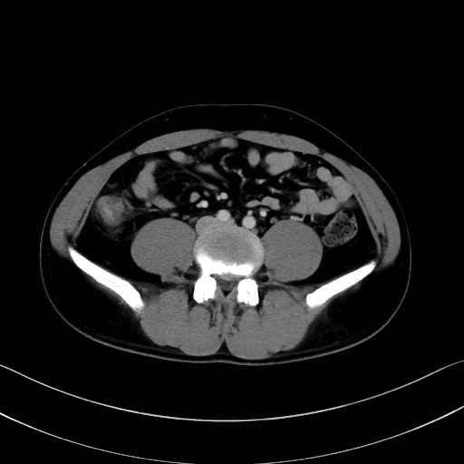

2. 腸腰筋群と骨盤底筋

大腰筋 (Psoas major)

腸骨筋 (Iliacus)